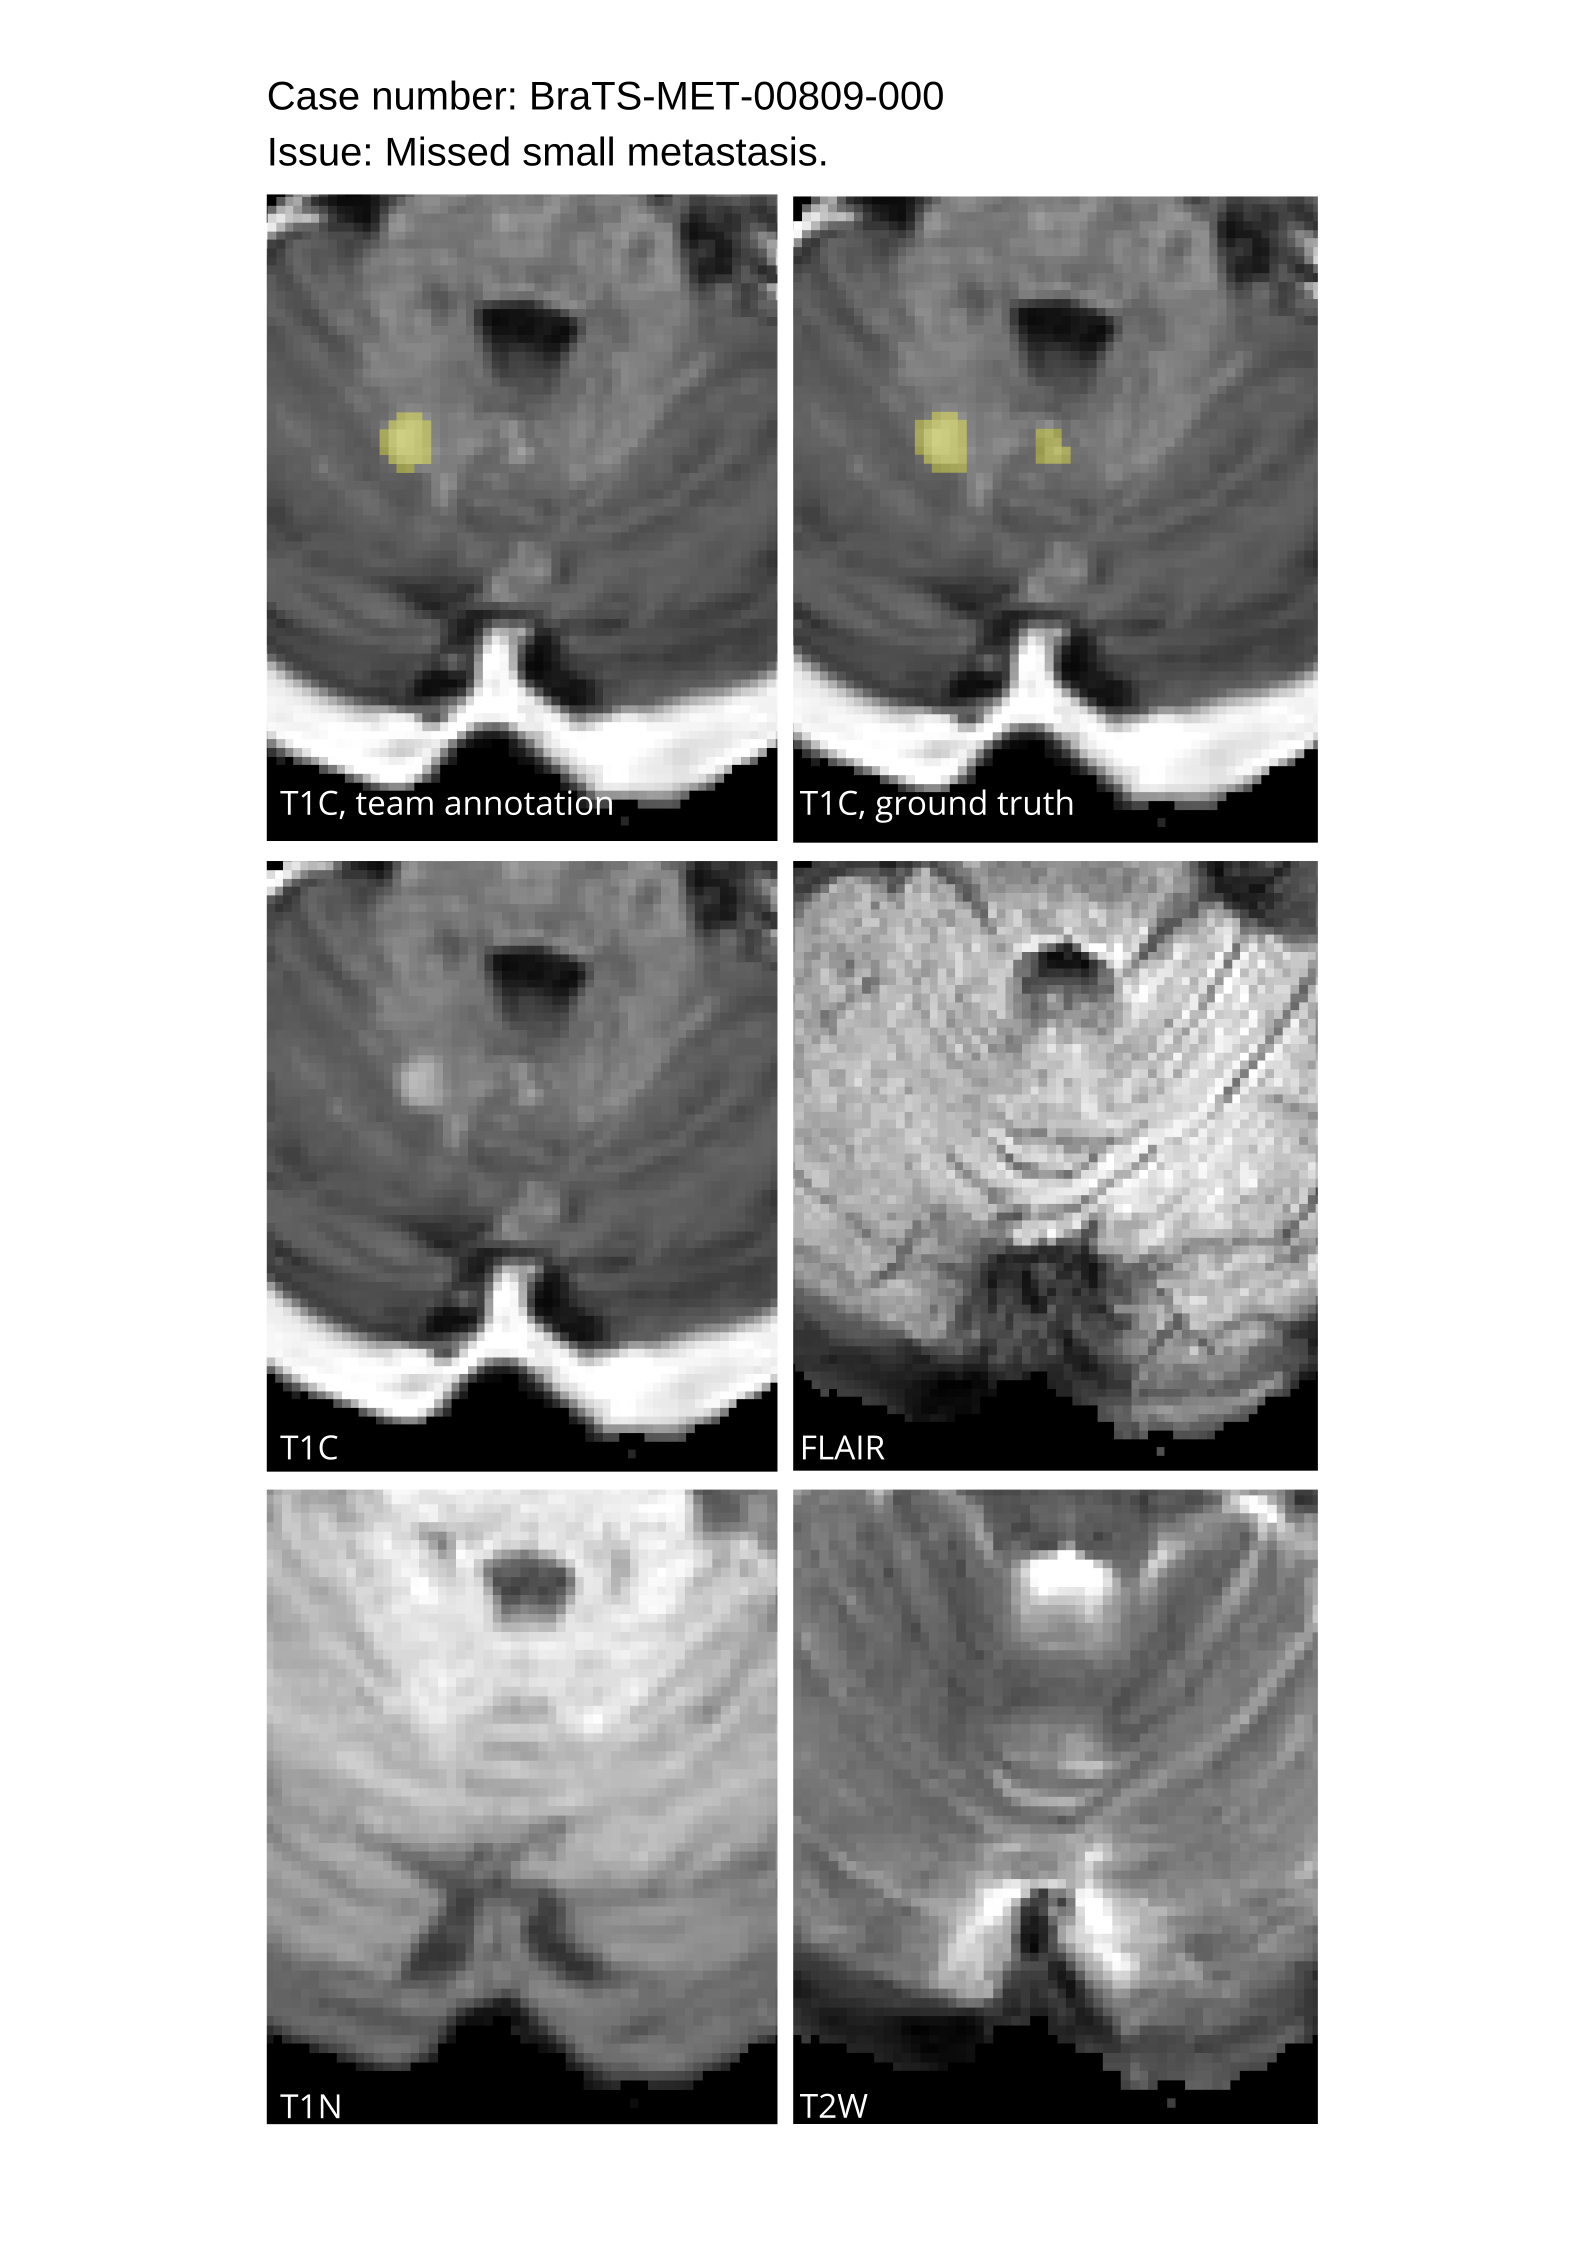

4.9 Common Errors of Automated Segmentations

Based on observations from previous BraTS challenges, common errors in automated segmentations were identified. The most typical errors in the current challenge included:

1. 1.

Automated algorithms missing small metastases. Enhancing metastasis was fused using the minority voting algorithm to aggregate all enhancing tumor voxels identified by the three algorithms. However, many small metastases were missed and were manually segmented by neuroradiology attendings.

2. 2.

Segmentation of white matter changes from microvascular disease. Peritumoral edema segmentations were checked by neuroradiology attendings and modified.

3. 3.

The segmentation of non-enhancing lesions that have intrinsic T1 hyperintensity. Voxels with intrinsic T1 hyperintensity were manually removed from ET segmentations.

These insights led to specific adjustments in the annotation process to enhance accuracy.